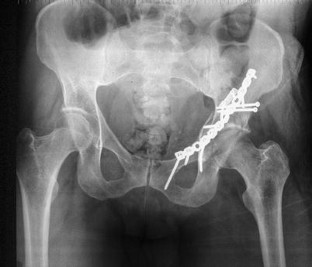

Es wird ein ungewöhnlicher Fall einer vorderen Pfeilerfraktur des Acetabulums mit ausgedehnter Impression im Bereich des hinteren Pfeilers beschrieben. Nach primärer Osteosynthese über einen ilioinguinalen Zugang erfolgt die Reposition der dorsalen Impressionen über einen hinteren Zugang mit Repositionskontrolle mittels chirurgischer Hütluxation.

An unusual case of an anterior column fracture of the acetabulum with extended marginal impaction at the posterior column is presented. Fracture fixation was primarily performed by an ilioinguinal approach followed by a posterior approach with surgical dislocation of the hip to reduce the impacted fragments.